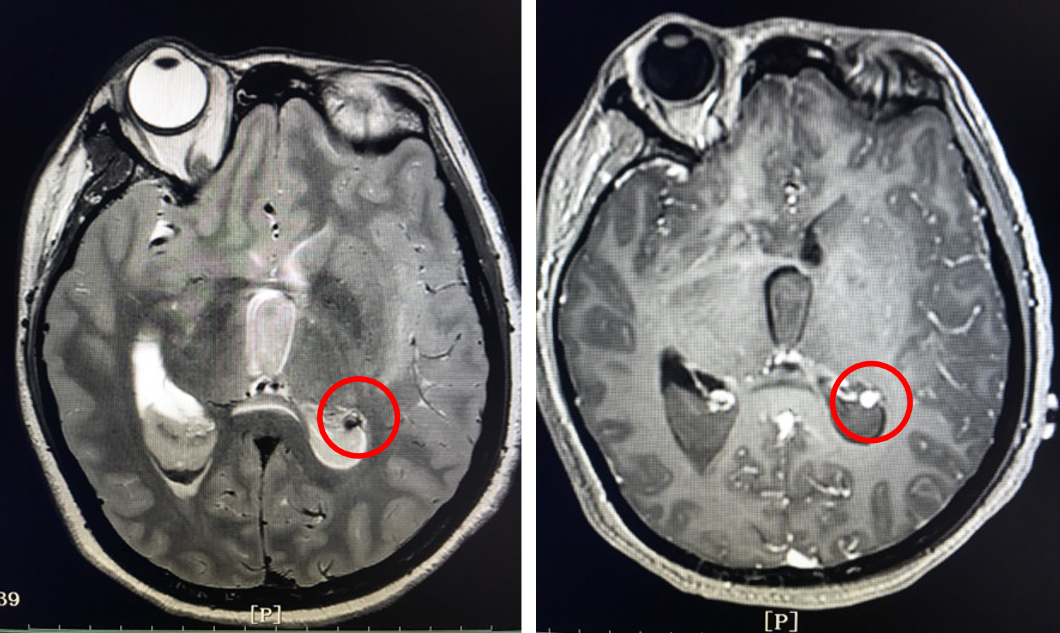

主诉:1月前突发剧烈头痛发作。

烟雾病

脉络膜前动脉假性动脉瘤

脑室旁动脉瘤较为罕见,文献中报告的病例不到60例,其中19例与烟雾病有关。大多数脑室旁动脉瘤继发于恶性高血压、感染或血管畸形,也有部分脑室旁动脉瘤是特发性的[1]。

有观点认为此类动脉瘤可以保守治疗,因为较小的脑室旁动脉瘤可能自发消退,但同样存在保守治疗的病例预后不佳[1-4]。深部动脉瘤通过血管内介入治疗往往能取得较好的疗效,治疗能否成功关键取决于载瘤动脉直径[5]。血管内栓塞通常是烟雾病患者脑室旁动脉瘤的首选方案,因为可以避免开颅手术对脑实质的损伤及相关的缺血事件发生[1]。在一项病例系列研究[6]中,血管内栓塞成功治疗了7例(88%)烟雾病伴脑室旁动脉瘤且无围术期并发症,其中6名患者在出院时完全康复(75%)。然而,烟雾病患者载瘤动脉往往十分迂曲,且动脉瘤容易破裂[5]因此血管内治疗往往充满挑战。显微手术夹闭是动脉瘤的传统治疗方法,但在治疗深部动脉瘤时,术中破裂的风险可能更高。微创手术如小骨窗和神经内镜已用于治疗颅内深部病变,并取得了不同程度的成功。

在本例病例中,针对脑室内动脉瘤,我们首选血管内治疗栓塞脑室旁动脉瘤,因为血管过于迂曲尝试失败。术后出现脑室内出血,于是启动备选方案,急诊在磁共振导航下通过endoport辅助进行动脉瘤切除,同时部分清除脑室内血肿并放置脑室外引流,降低远期脑脑积水的风险。随着神经内镜的普及,深部的脑血管病变的治疗方案有了更多的选择,而充分的术前评估与周全的手术方案规划是手术安全与成功的基石。